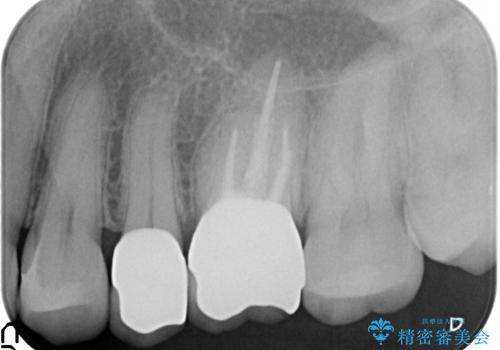

- 左上4、5、6番目の歯を白くしたいといらっしゃった方の症例です。

4番目の歯はセラミックインレーによる修復、5・6番目の歯はオールセラミッククラウンによる補綴を行いました。

左上6番目の歯については再根管治療を行っております。